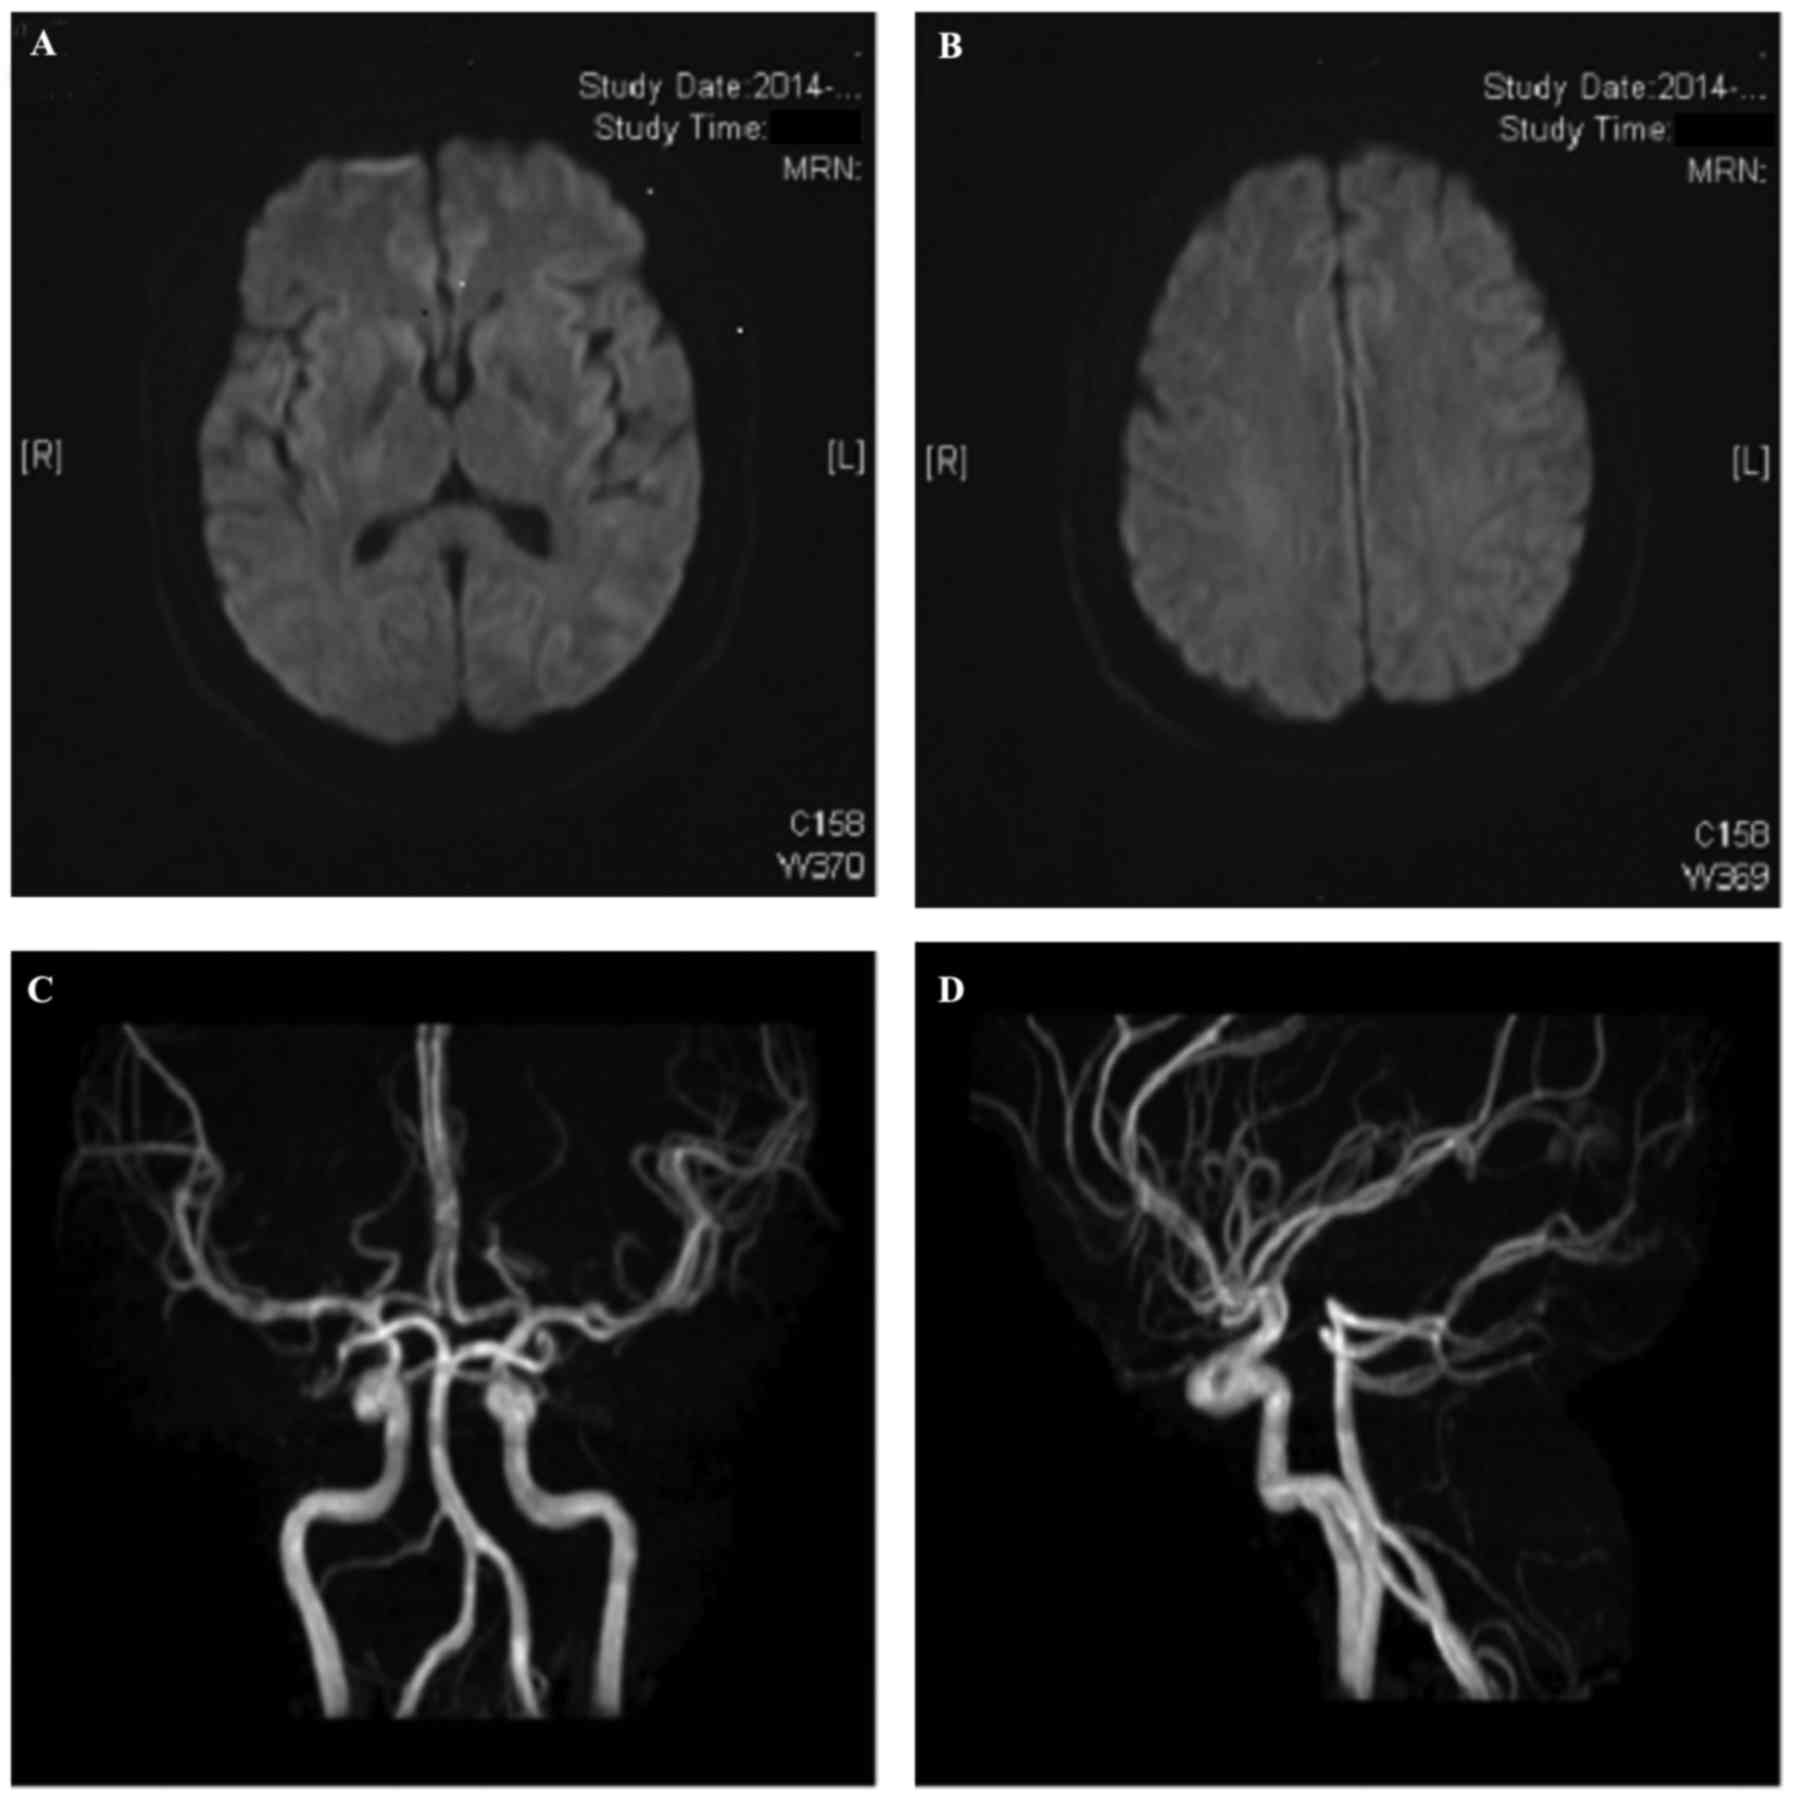

The present case report described a patient with thrombotic thrombocytopenic purpura (TTP), who presented to the China‑Japan Union Hospital of Jilin University (Changchun, China), and the changes in plasma von Willebrand factor (vWF) and vWF cleaving protease (vWF‑cp) observed during treatment. Computed tomography and diffusion‑weighted magnetic resonance (MR) imaging of the brain, cerebral MR angiography and other experimental tests were performed and the patient was subsequently diagnosed with TTP. The patient underwent treatment with plasma exchange, glucocorticoids and supportive care. Hematologic and biochemical parameters began to gradually improve over the 12 days after admission; platelet count, serum creatinine and serum lactate dehydrogenase concentrations returned to their normal ranges, plasma vWF concentration decreased to normal levels over the 30 days after admission, and vWF‑cp activity increased compared with the levels detected in healthy volunteers. Monthly rituximab treatment was administered 4 times following patient discharge to prevent relapse, and no recurrence was detected at the 20‑month follow‑up. Plasma exchange therapy is effective in patients with TTP. After low‑dose rituximab treatment, recurrent TTP has not been detected found till now. In the present case, vWF concentration and vWF‑cp activity were measured at 8, 10, 23 and 32 days after admission; compared with the control group, patient's vWF concentration gradually decreased and vWF‑cp activity slowly increased, suggesting that the patient had a favorable prognosis and a low risk of recurrence.